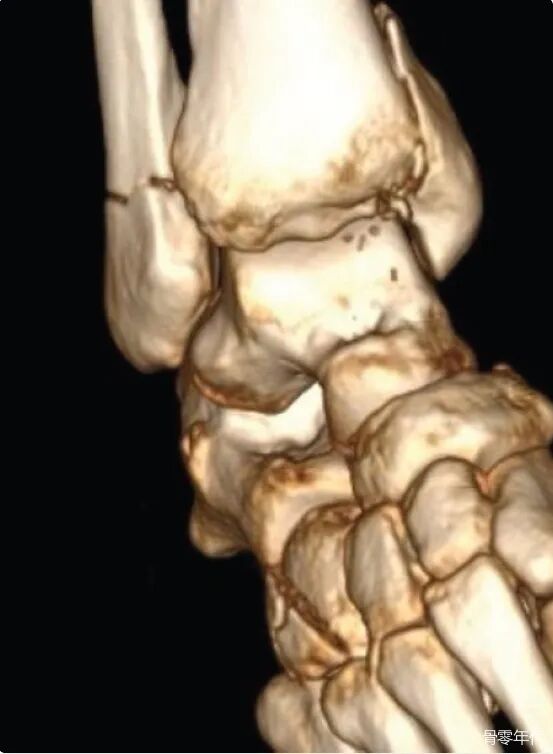

影像学表现